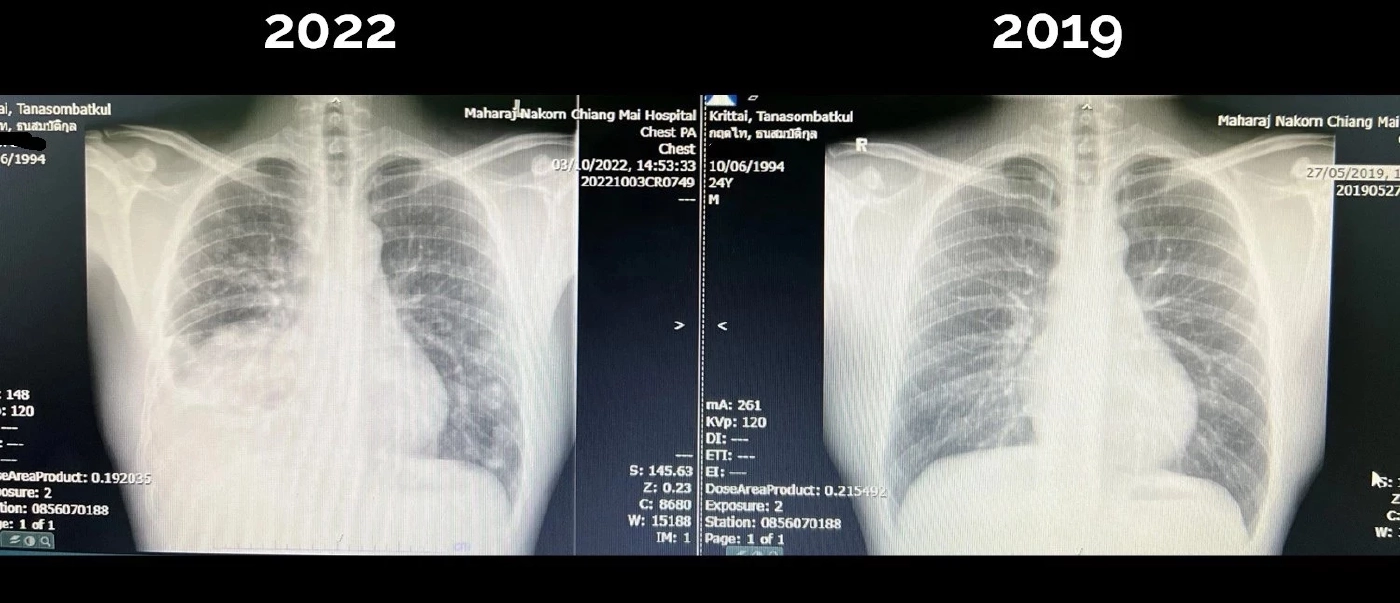

ความตั้งใจของผม มีแค่การเขียนเล่าเรื่องราวและส่งต่อพลังให้กับคนอื่นเท่านั้นครับ แต่ ผมจำเป็นต้องบอกตามตรงว่า "ขณะนี้ผมเองอยู่ในกระบวนการรักษา” ยังต้องรับยาเคมีบำบัด ณ วันที่พิมพ์อยู่นี้ ผมก็ยังคงปวดหัว อ่อนเพลีย ผมร่วง และภูมิคุ้มกันต่ำ